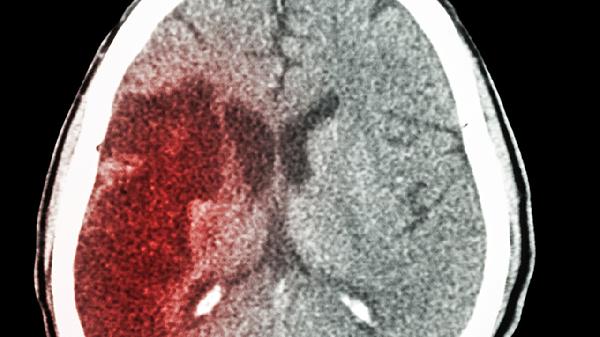

丘脑出血后遗症可通过康复训练、药物治疗、物理治疗、心理干预、手术治疗等方式治疗。丘脑出血后遗症通常由神经功能缺损、脑水肿、脑积水、继发感染、心理障碍等原因引起。

手术治疗主要用于解决丘脑出血后遗症引起的严重并发症。脑室腹腔分流术可治疗脑积水,缓解颅内压增高。血肿清除术可清除残留血肿,减轻对周围脑组织的压迫。手术需由神经外科医师评估后决定,术后需密切观察病情变化。